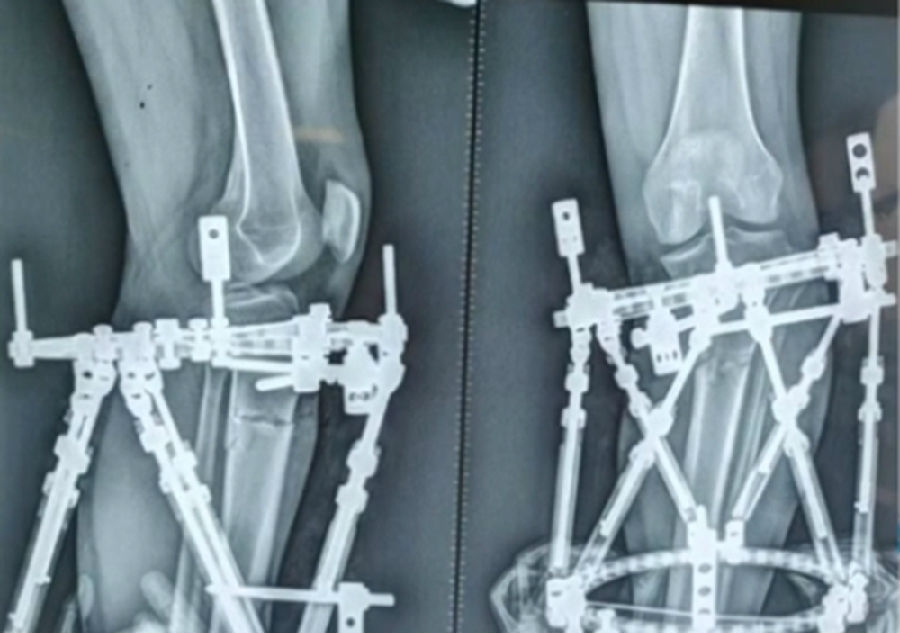

典型病例,女性,56岁,农民右膝内翻18度。

术前影像

术中影像

结合影像学来看,该患者单纯用闭合截骨或开放截骨,对肢体均有影响,所以决定采用混合型截骨。术中混合截骨旋转中心选在内外1/3处,先做闭合楔,然后顺势将开放楔敲开,达到术前设计的目标力线。术后随访力线达到要求。

术后X线